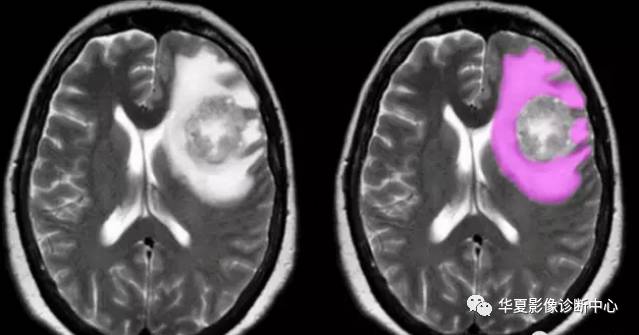

血管源性脑水肿

好发于脑肿瘤,出血,创伤或炎症等。多分布于脑白质区域。

MR表现:常呈手指状分布,长T1长T2信号,DWI不呈高信号,ADC常高于正常脑组织。

水肿呈长T2信号,肿瘤周缘水肿局限于白质,灰质未明显累及。